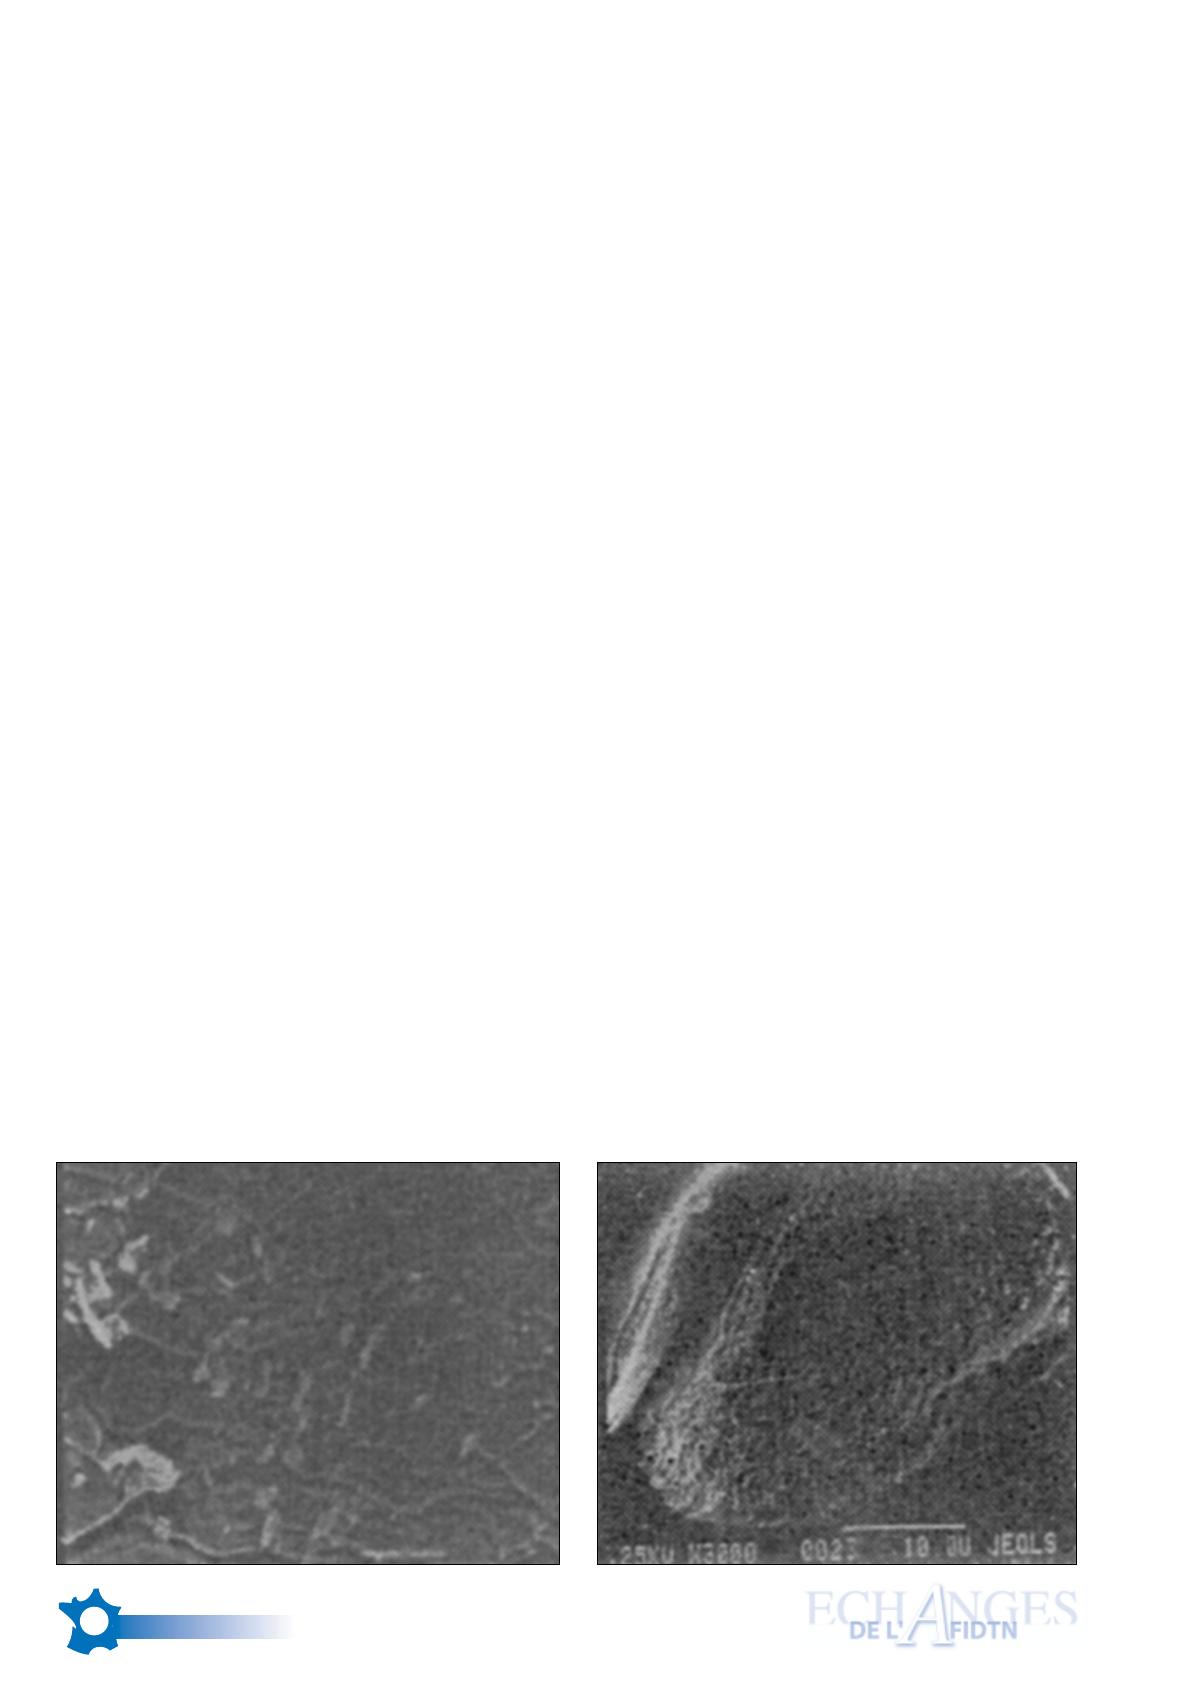

Chaque bactérie peut ainsi créer une

colonie visible en microscopie électro-

nique sous forme de “galette”. L’extension

se fait par essaimage d’une bactérie en

dehors de cette galette qui va créer une

nouvelle colonie dite “colonie fille” qui

sera elle-même à l’origine d’une nouvelle

galette et ainsi de suite pouvant aboutir à

un véritable tapis bactérien (Fig. 2

ci-dessous).

Fig.2 : Exemple de colonisation bactérienne d’un matériau inerte (2ème image : une “galette” à fort grossissement)